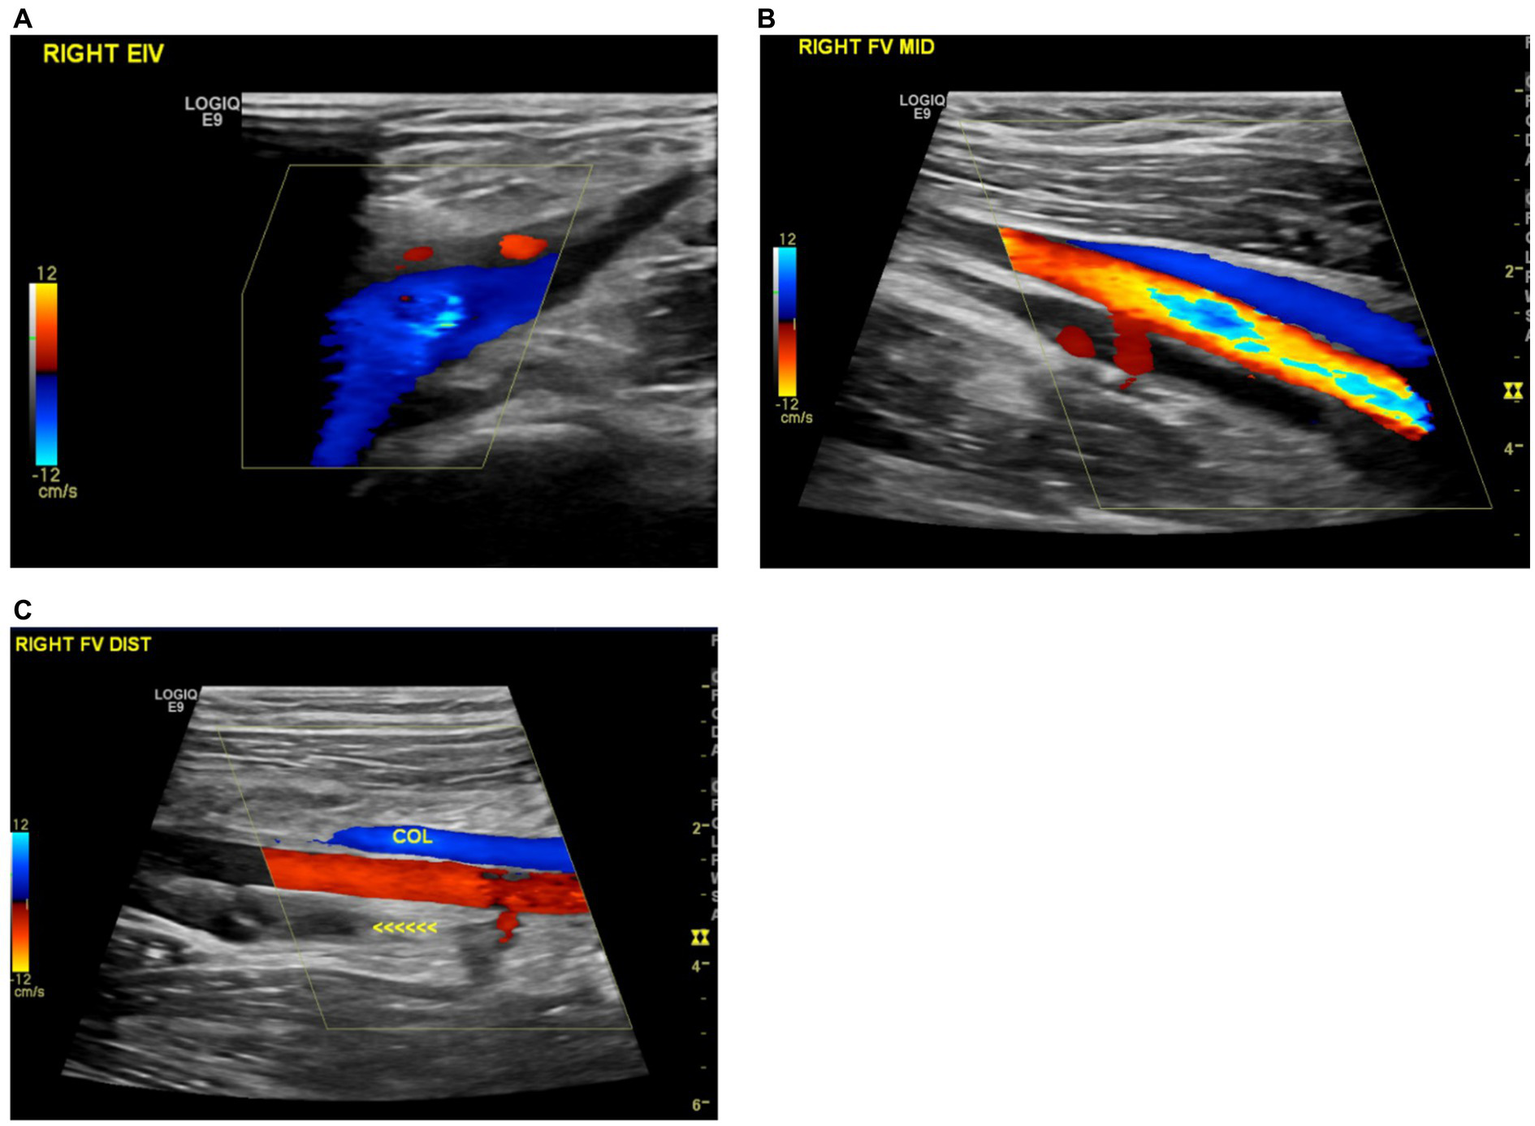

Figure 3

(A) Recanalization of the previously thrombosed right external iliac vein. (B) Improved recanalization observed in the mid-section of the right superficial femoral vein. (C) Formation of a new collateral vein in the right distal femoral vein.

During the fifth follow-up at 24 weeks post-diagnosis, the patient experienced a relapse, evidenced by progressive swelling in the bilateral lower limbs and the right upper limb. Doppler ultrasounds confirmed these findings (Figure 2). In response, the prednisolone dose was increased from 20 mg to 50 mg (i.e., 1 mg/kg) with continuation of azathioprine 100 mg (i.e., 2 mg/kg). Given the recurrent relapses of the disease, infliximab 5 mg/kg injections were initiated on a schedule of 0, 2, 4 weeks, followed by every 6 weeks thereafter. As of the current time, the patient has received a total of eight infliximab injections and is being maintained on azathioprine 100 mg daily. This regimen has resulted in marked clinical improvement, with an absence of active symptoms. Furthermore, ultrasound imaging of both the upper and lower extremities has revealed significant vascular recanalization with multiple collaterals (Figure 3).